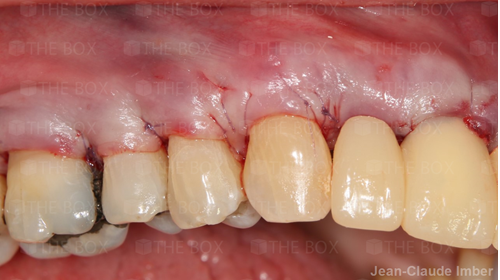

A new case was made public by Jean-Claude Imber check it out here.